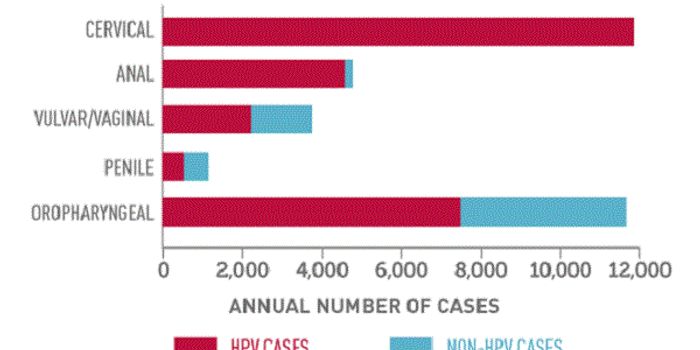

APR 15, 2015Health & MedicineMaking the decision to move from co-testing to primary Human papillomavirus (HPV) screening was one thing. Implementing ...

APR 15, 2015CancerThe human immune system is poised to spring into action at the first sign of a foreign invader, but it often fails to el ...